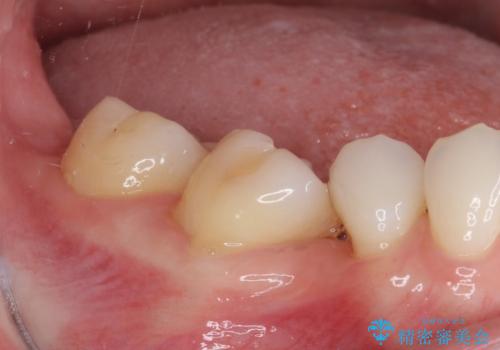

- 上下前歯のデコボコと奥歯の欠損を気にして来院された患者様です。

右下の欠損分は奥歯が倒れ込んでスペースがなくなっていたため、矯正治療により本来の位置に歯を移動させ、オールセラミックブリッジによる欠損補綴治療を行うこととしました。

全顎的にセラミッククラウンが多く装着されているため、インビザラインによる矯正治療を行うこととしました。